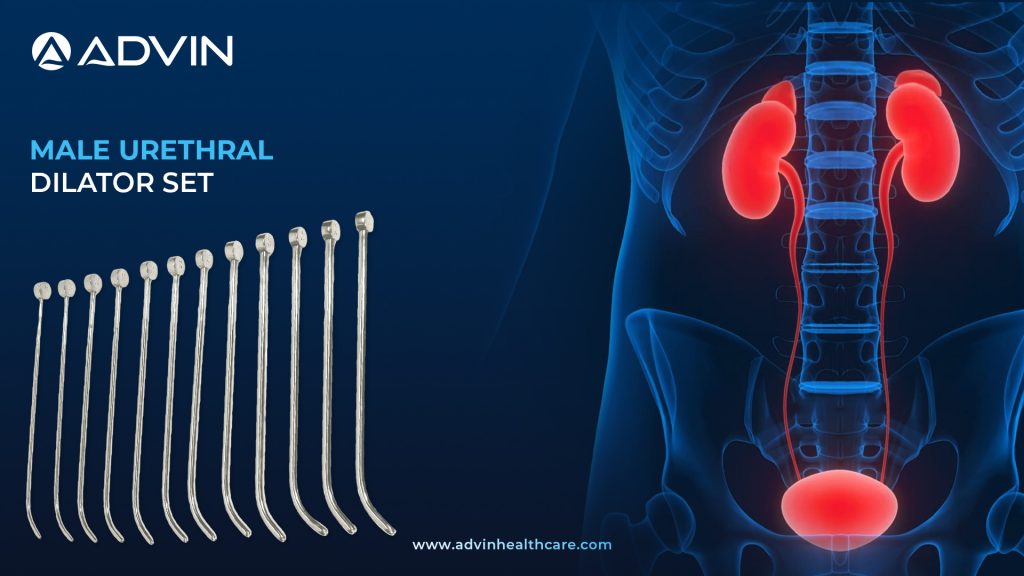

Male Urethral Dilator Set – Reliable Tools for Accurate Stricture Management

Introduction to Male Urethral Dilator Set: Essential Tool for Urethral Stricture Management The Male Urethral Dilator Set is used to treat urethral strictures by gradually expanding the narrowed urethral passage. It includes a series of dilators in increasing sizes to restore normal urinary flow. This is a standard urology instrument...